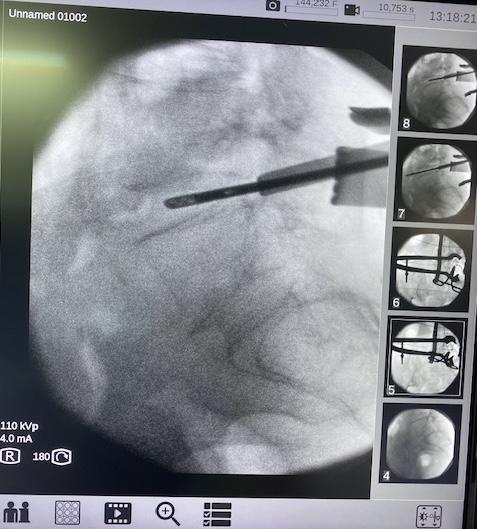

HERNIA DISCAL LUMBAR: en función del caso y las características del paciente, podemos realizar cirugía ENDOSCÓPICA (con unos pequeños orificios y la ayuda de la microcámara eliminamos la hernia discal) o la MICRODISCECTOMIA (una pequeña incisión y la ayuda de un retractor especial para visualización directa y eliminación de la hernia discal). Ambas cirugías tienen una hospitalización corta de 24-48 horas y una recuperación en pocas semanas.

Microdiscectomía lumbar

Microdiscectomia lumbar